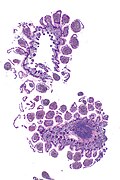

Case 2

- Pseudomelanosis ileum -- very low mag.jpg

PI - very low mag. (WC)

- Pseudomelanosis ileum -- low mag.jpg

PI - low mag. (WC)

| LM | dark pigment in the lamina propria macrophages |

- Dark pigment in the lamina propria macrophages.